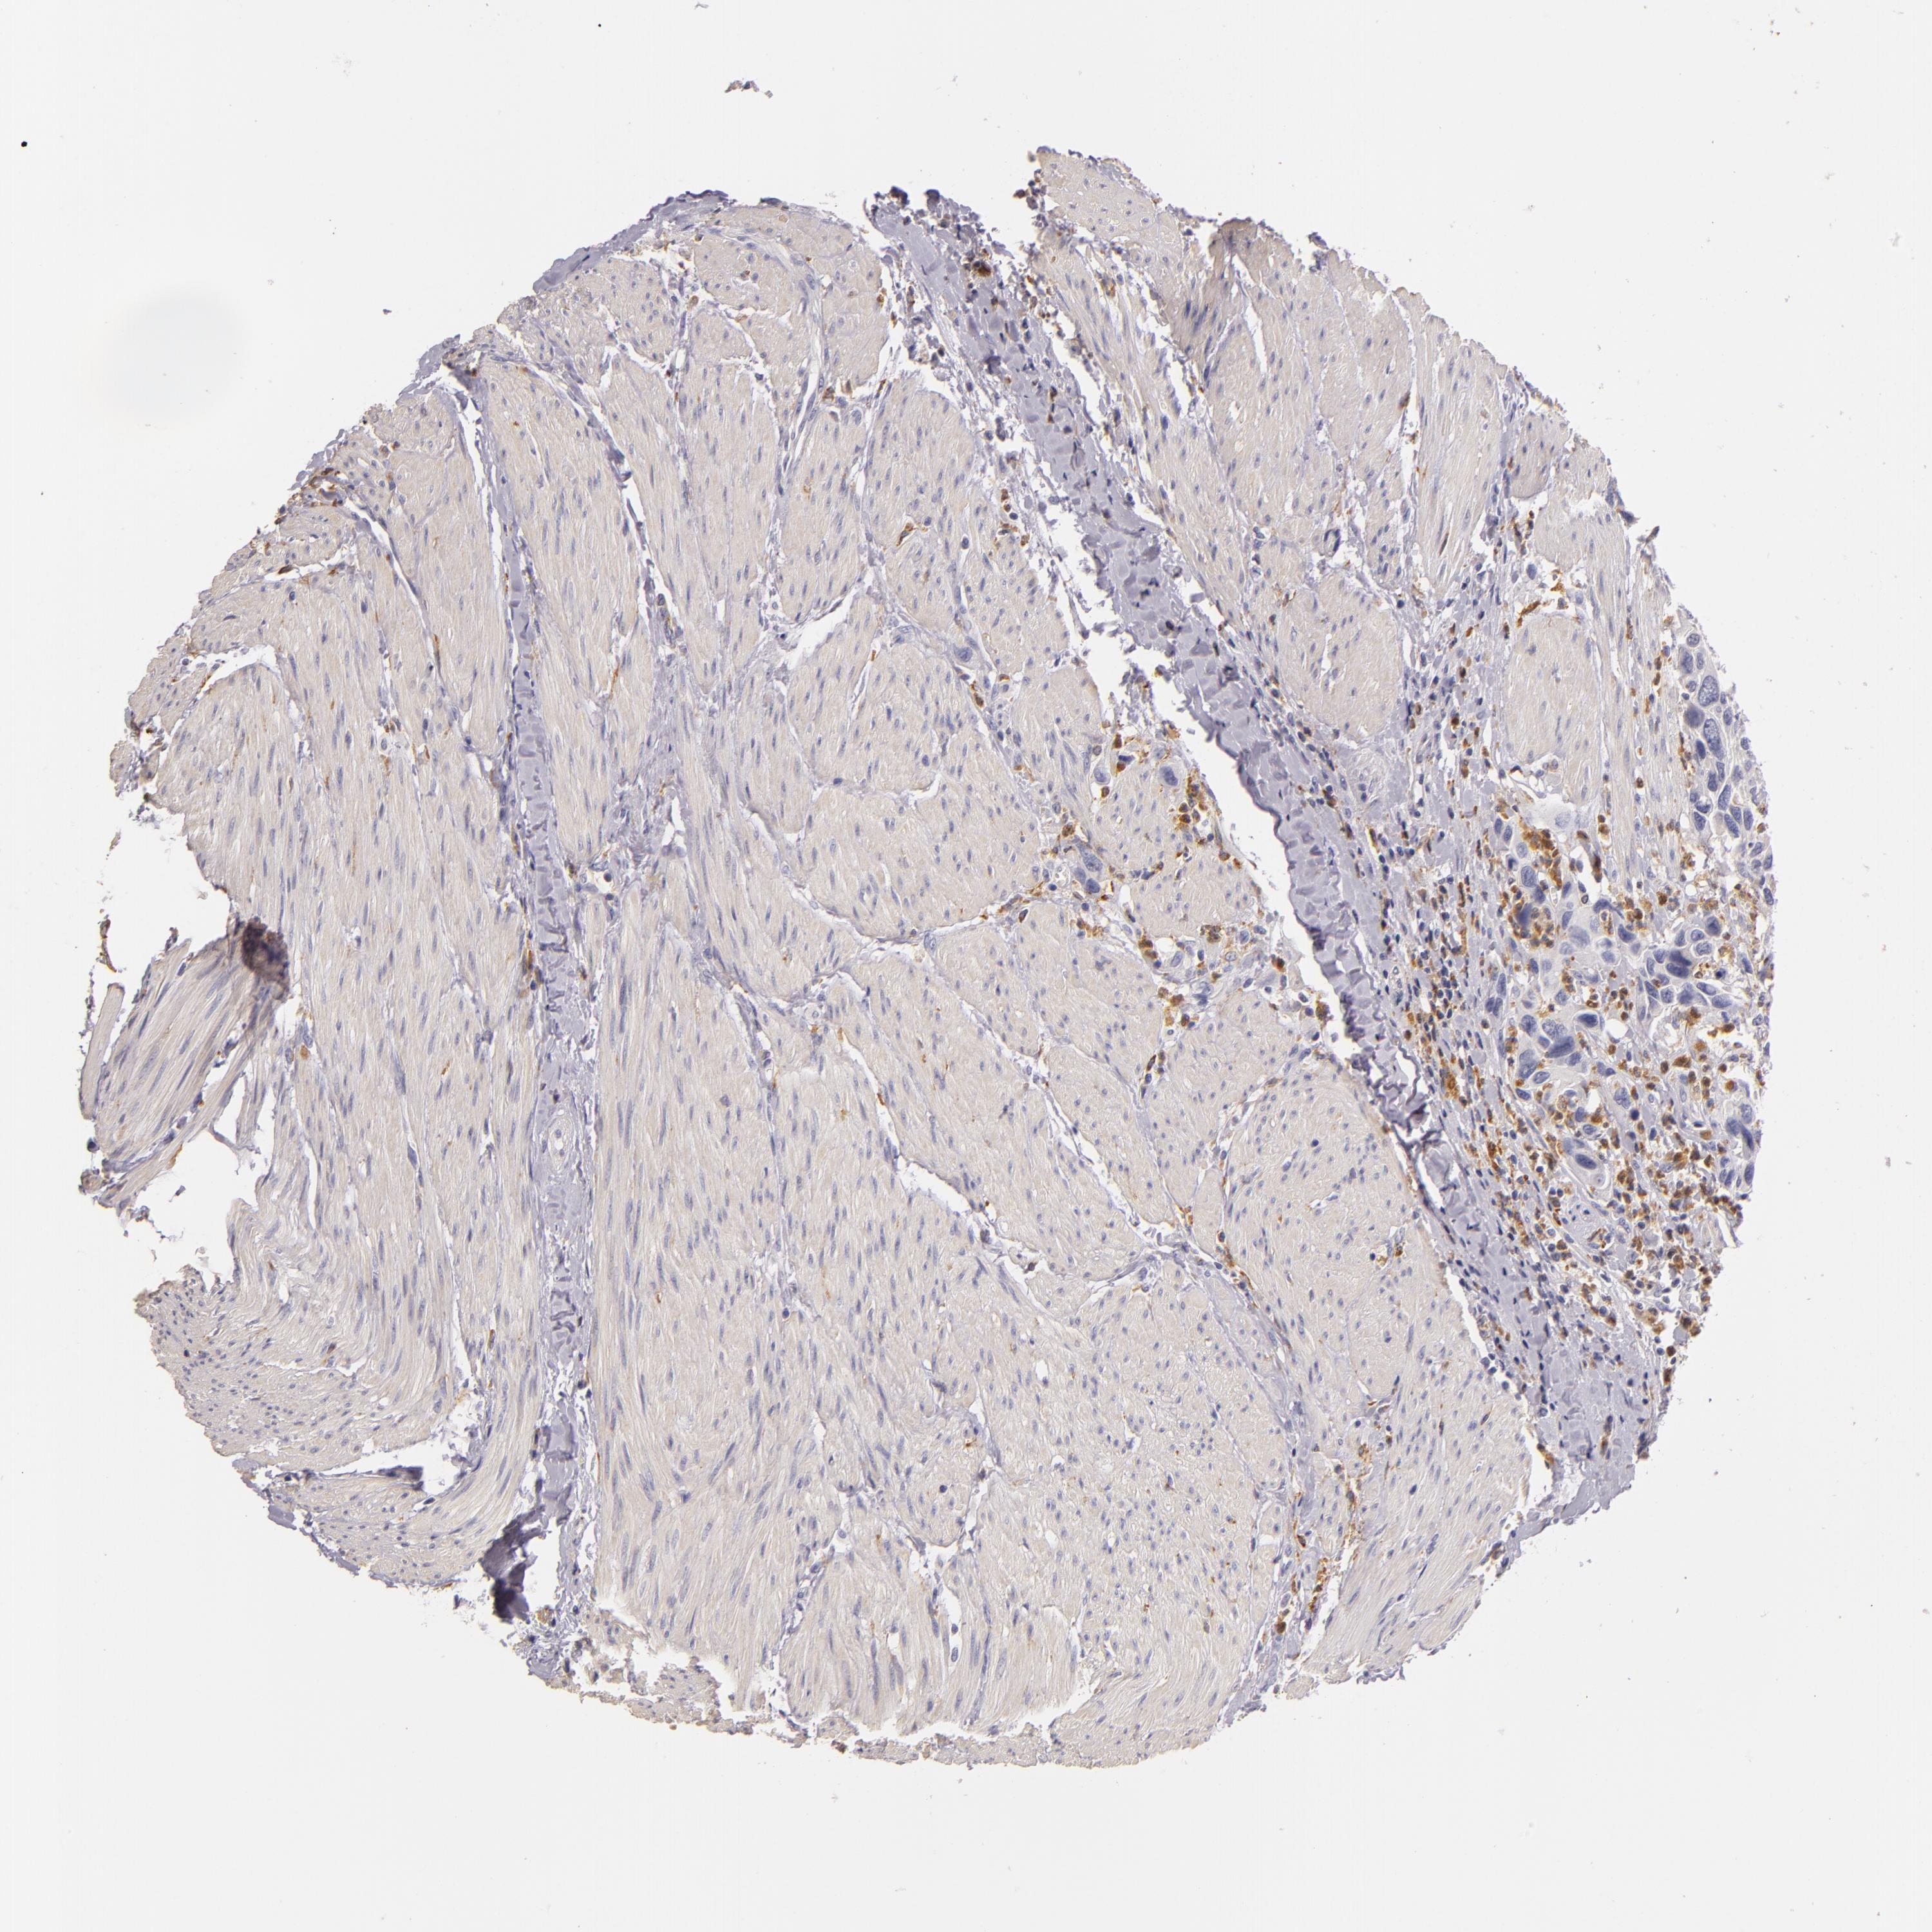

UROTHELIAL CANCER - Protein expressioni

A mouse-over function shows sample information and annotation data. Click on an image to view it in a full screen mode. Samples can be filtered based on level of antibody staining by selecting one or several of the following categories: high, medium, low and not detected. The assay and annotation is described here.

Note that samples used for immunohistochemistry by the Human Protein Atlas do not correspond to samples in the TCGA dataset.

Antibody stainingi

Antibody staining in the annotated cell types in the current human tissue is reported as not detected, low, medium, or high, based on conventional immunohistochemistry profiling in selected tissues. This score is based on the combination of the staining intensity and fraction of stained cells.

Each image is clickable and will lead to virtual microscopy that enables deeper exploration of all samples and also displays staining intensity scores, fraction scores and subcellular localization as well as patient and tissue information for each sample.

Antibody HPA001608

Staining

High

Medium

Low

Not detected

Intensity

Strong

Moderate

Weak

Negative

Quantity

>75%

75%-25%

<25%

None

Location

Nuclear

Cytoplasmic/membranous

Cytoplasmic/membranous,nuclear

Urothelial carcinoma, Low grade